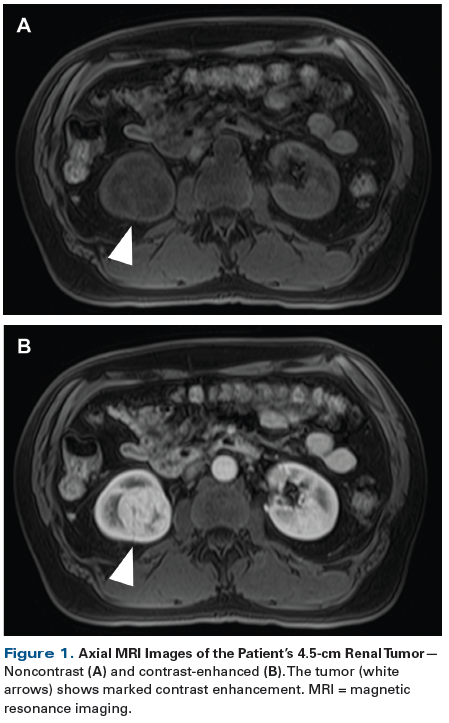

Figure 1. Axial MRI Images of the Patient’s 4.5-cm Renal Tumor

A 56-year-old man presented with a 4.5-cm leftsided renal mass incidentally discovered on an ultrasound performed for workup of lupus nephritis. On dedicated contrast-enhanced magnetic resonance imaging (MRI), the tumor was found to be avidly enhancing (Figure 1). In light of the patient’s history of lupus nephritis and related concerns over future declines in renal function, the patient elected to undergo renal mass biopsy prior to deciding on the mode of treatment. A core needle biopsy was performed and pathologic review of the specimen demonstrated an oncocytic renal neoplasm (Figure 2).